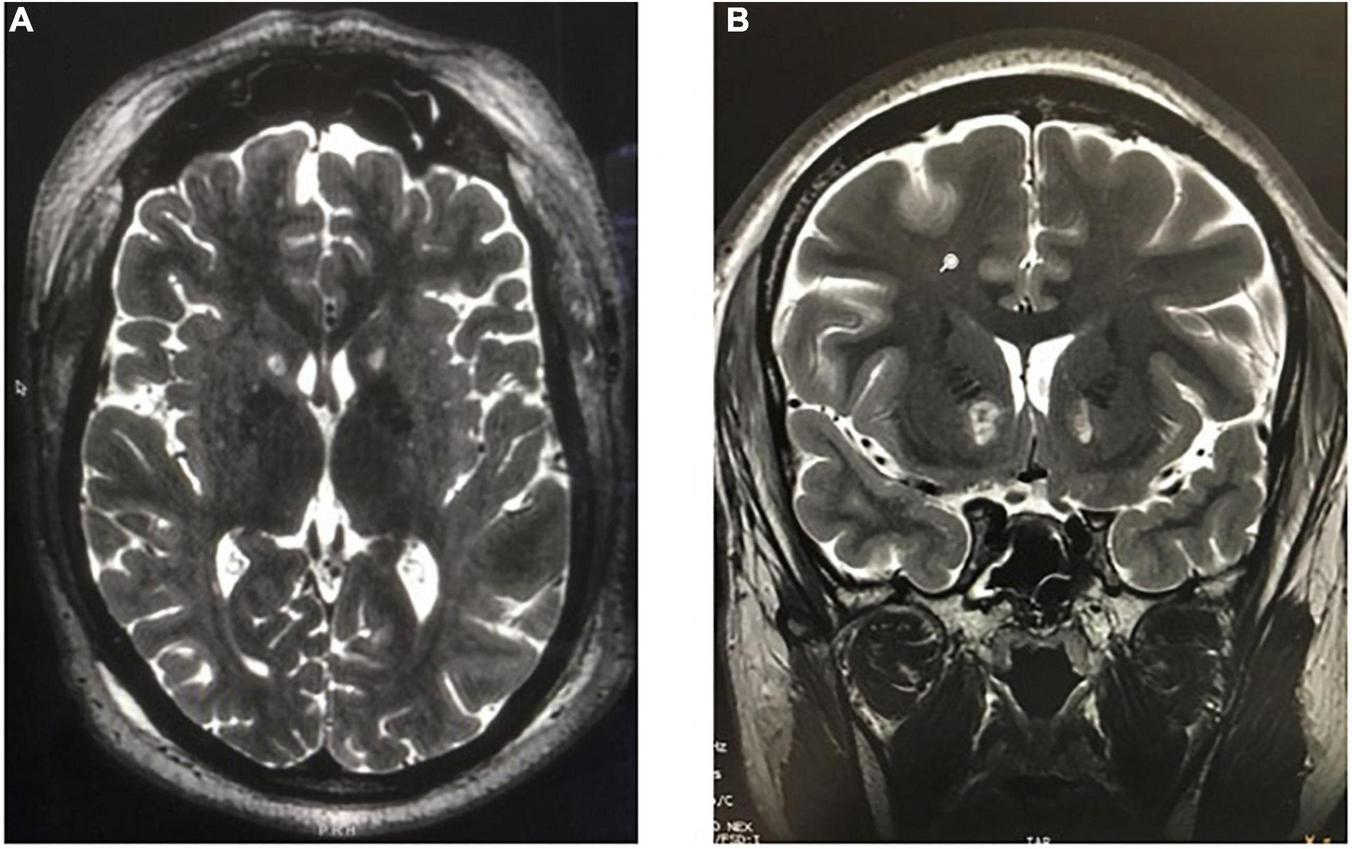

Another recently developed non-invasive lesioning technique for refractory OCD or MDD is MR-guided focused ultrasound (MRgFUS). In this procedure, a stereotactic head frame is applied with local anesthesia to the patient’s shaved head and secured in a commercially manufactured helmet embedded with 1,024 ultrasound transducers (ExAblate Neuro; InSightec Inc., Haifa, Israel) within the MRI scanner. In MRgFUS for OCD or MDD, the anterior capsule is directly targeted, and the target area is heated to 50–60°C for several seconds under real-time MR-thermometry monitoring (Davidson et al., 2020a; Figure 11).

FIGURE 11

MR-guided focused ultrasound capsulotomies (MRgFUS). (A) Axial T2-weighted and (B) Coronal T2-weighted MRI after bilateral MRgFUS capsulotomy.

A proof-of-concept study of MRgFUS anterior capsulotomy in 4 patients with treatment-resistant MDD found significant symptom relief in 3 of 4 patients within 1 week, and at least a 50% reduction in hamilton depression rating scale (HDRS) scores in all patients at 12-month follow-up (Jung et al., 2015). A follow-up study of 11 patients who underwent MRgFUS anterior capsulotomy for medically refractory OCD showed significant reduction in YBOCS and HDRS scores at 2 years (Kim et al., 2018). In 16 patients who underwent MRgFUS capsulotomy for MDD or OCD, no serious adverse events occurred, although in six additional patients, lesions could not be made due to limiting skull densities (Davidson et al., 2020a). At 6-month follow-up, six of the 12 patients who had undergone MRgFUS capsulotomy and reached 6-month follow-up showed clinical response, defined as a reduction of at least 35% on the YBOCS score (for patients with OCD) or a reduction of at least 50% on the Hamilton Depression Rating Scale (HDRS) (for patients with MDD) (Davidson et al., 2020a). Two phase I trials of MRgFUS anterior capsulotomy for MDD (n = 6) and OCD (n = 6) found response rates of 2 of 6 patients with OCD and 4 of 6 patients with MDD, respectively (Davidson et al., 2020b). Overall response rate and magnitude of response to MRgFUS capsulotomy are comparable to SRS capsulotomy, but the interval to response is much shorter with MRgFUS. Going forward, diffusion tensor imaging (DTI) may be used to achieve more patient-specific targeting of the tracts in the anterior limb of the internal capsule for capsulotomies, with the potential for even better outcomes (Avecillas-Chasin et al., 2019).